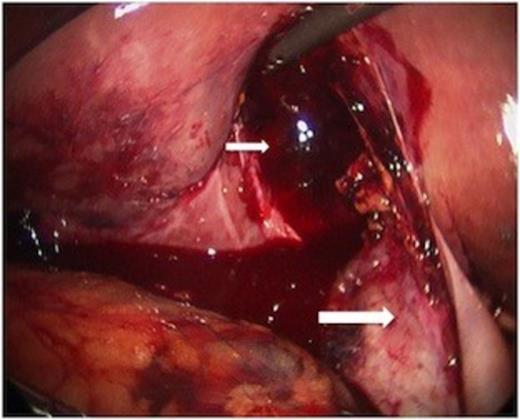

Minimal additional blunt dissection exposed the cystic artery and duct. A critical view of safety was achieved so that cholecystectomy could be performed. Only a small amount of oozing was noted from the liver laceration, following removal of the gallbladder. Haemostasis was achieved with topical agents. The pathologic specimen showed acute inflammation with perforation (Figure 4).